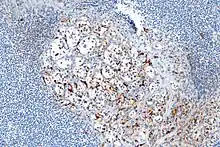

- About 40% of carcinoids have a scattering of sustentacular cells, which stain positive for S-100.[6]